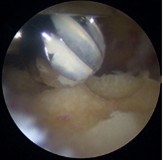

半月板は膝の内側と外側の両方に存在してクッションの役目を果たしており、外傷やスポーツなどによるオーバーユースにより損傷することがあります。また加齢による変性でも損傷します。手術では関節鏡を膝関節内に挿入して半月板の様子を確認してどのような手術を行うかを判断します。当院ではなるべく半月板を温存することを心掛けており、半月板縫合を行うことが多いですが、修復が難しい部位では部分切除が余儀なくされることもあります。

鏡視下膝半月板形成術

修復前

修復後(フィブリン+人工靭帯使用)